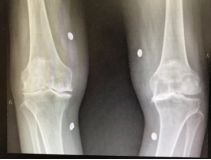

这次也是经人介绍来普陀区中心医院骨科周军杰大夫的专家门诊,原本想配点药吃吃,减轻点疼痛就算了。可是周军杰主任医师一看情况就发现不妙,双侧的膝盖都已经内翻畸形,关节伸屈活动度只有正常的一半都不到,就果断给拍了X光片,一拍片子就知道原来两侧的膝盖都已经到了骨关节炎终末期,严重内翻畸形,看来只能手术,否则情况只会越来越糟糕。

图1 膝关节X光片(可滑动)